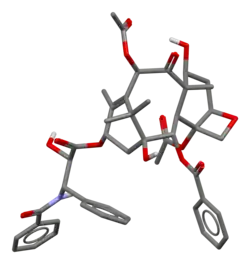

Space-filling model of paclitaxel

Space-filling model of paclitaxel Rotating paclitaxel molecule model

Rotating paclitaxel molecule model Crystal structure of paclitaxel

Crystal structure of paclitaxel Total charge surface of taxol. Minimum energy conformation.

Total charge surface of taxol. Minimum energy conformation.